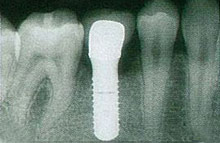

インプラント埋入手術を安全にかつ長い期間安定させるためには、骨の形が重要な要素となります。

具体的には三次元的に診断を行い、骨の「高さ」と「幅」がインプラントに適した形である事が必要とされます。

骨が大きく欠損しており、高さおよび幅の形が適切ではないとインプラントを埋入する角度を傾けざるを得ず良好な形態のインプラントの冠を装着できない可能性があります。

また高さが足りない場合には、短いインプラントしか埋入できず、長期的に見て、機能負荷が掛かりすぎ、長い期間の安定が得られない可能性が考えられます。